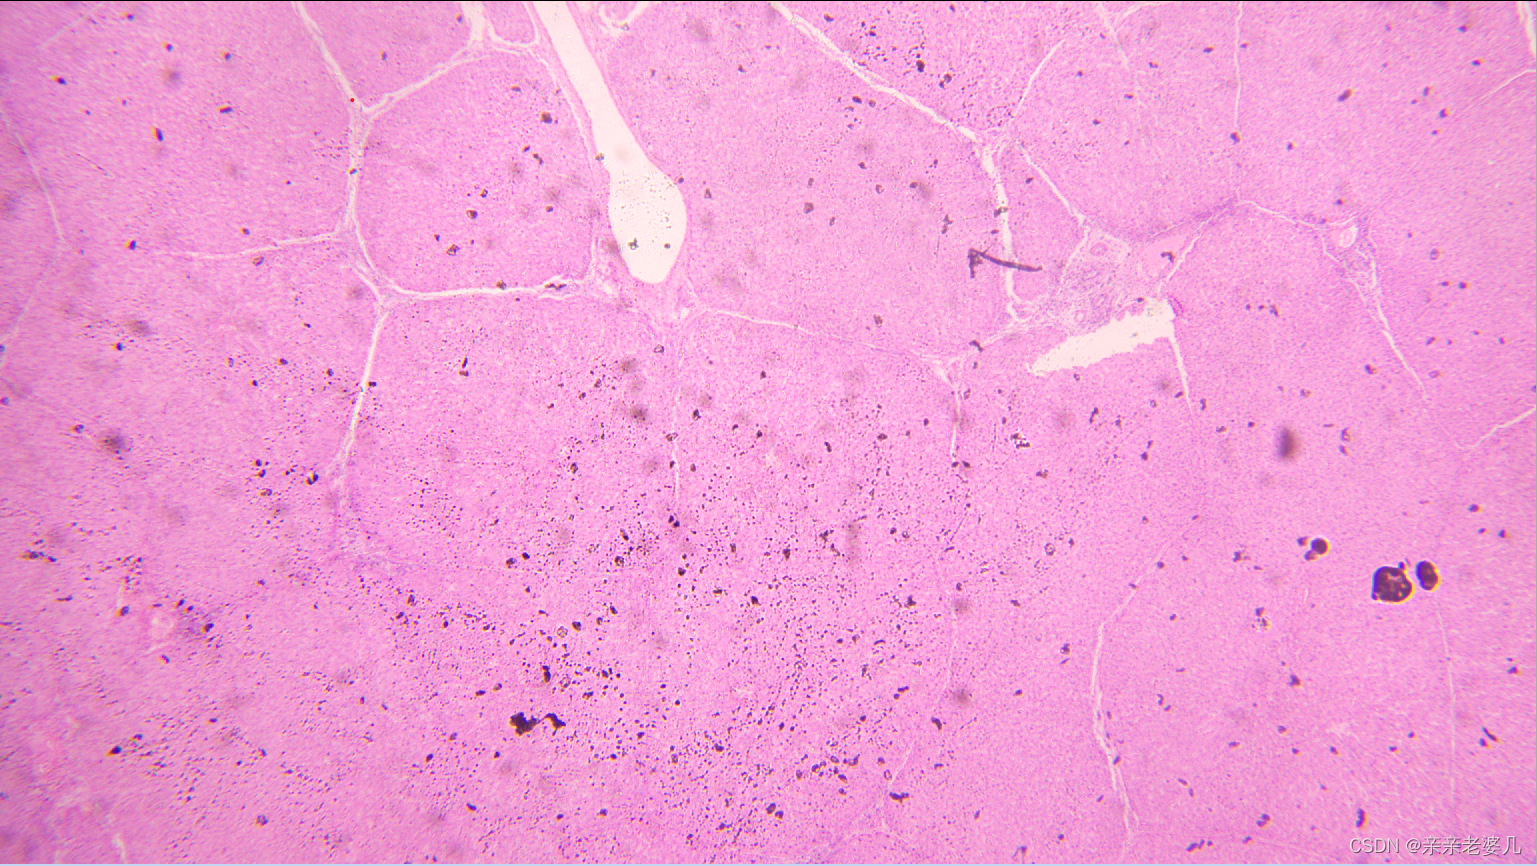

9. 千奇百怪的疾病——疾病的显微诊断及大体实物标本展示

如何获得标本:

手术 取材 包埋 蜡块 切片 染色

肠腺癌

肺水肿

肝癌

宫颈鳞癌

正常大肠

正常肺

正常肝

正常小肠